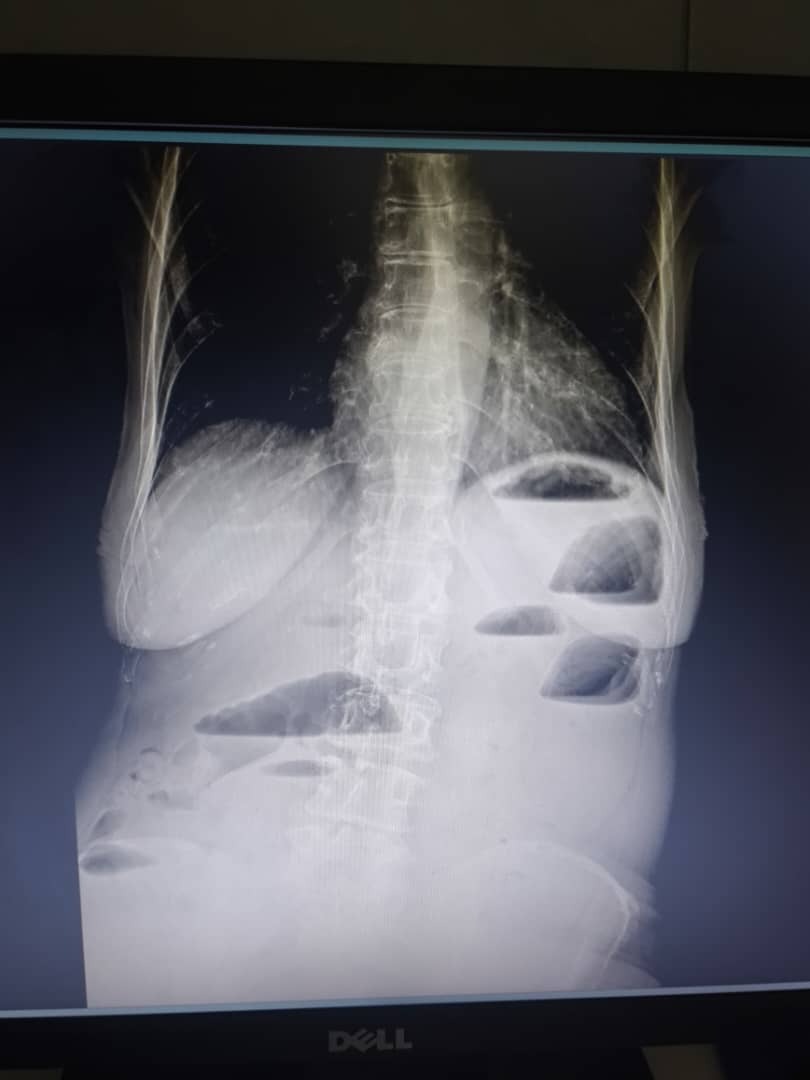

Estuvo más de 11 días vomitando y descompensada, mientras los médicos inicialmente pensaban que era una virosis. Al no mejorar, un internista indicó que podía tratarse de una úlcera péptica y pseudo obstrucción, pero los síntomas continuaron. Buscamos una segunda opinión médica y, tras varios exámenes, descubrieron que tenía múltiples obstrucciones intestinales, probablemente causadas por una cirugía que tuvo hace más de 15 años.

For over 11 days, she was vomiting and deteriorating, while doctors initially suspected a viral infection. As her condition worsened, an internist suggested a possible peptic ulcer and pseudo-obstruction, but her symptoms persisted. A second medical opinion and further tests finally revealed multiple intestinal blockages, which had likely been developing for years — possibly a complication from a surgery she had over 15 years ago.

Para entonces, ya estaba extremadamente débil y desnutrida, porque su cuerpo no podía absorber nutrientes. Fue ingresada de urgencia en el hospital El Llanito, donde la operaron y ahora permanece en cuidados intensivos, en estado delicado. A esto se suma que padece artritis reumatoide crónica, derivada de una infección por chikungunya, lo que complica aún más su recuperación.

By that point, she was already extremely weak and malnourished, as her body couldn’t absorb nutrients. She was admitted urgently to El Llanito Hospital, where she underwent surgery and remains in the ICU, in a delicate state. To complicate things further, she also suffers from chronic rheumatoid arthritis, a condition triggered by a past chikungunya infection.